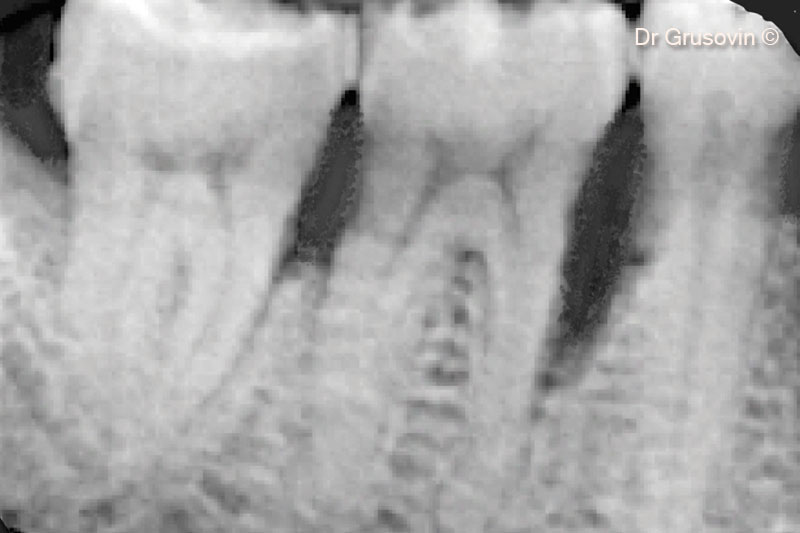

3. X-ray #16